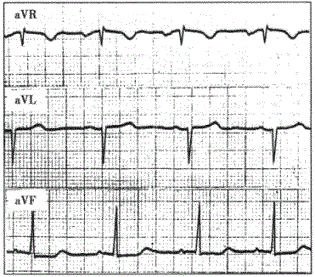

问题 患者男性,68岁,慢性肺源性心脏病。心电图如下图所示,应诊断为

选项 A.不完全性右束支阻滞 B.完全性右束支阻滞 C.后壁心肌梗死 D.右心室肥大伴劳损 E.不完全性右束支阻滞合并右心室肥大

答案 D

解析 :图中见窦性P波规律出现,额面QRS心电轴右偏,V导联QRS波群呈R型,R>1.0mV,T波倒置,V导联S波变深,符合右心室肥大伴劳损的心电图改变。